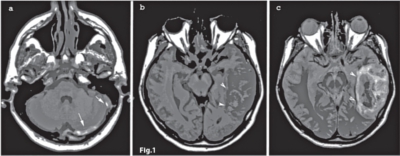

• stadiul II (subacut între ziua a 6-a şi a-15 zi: metHb intracelulară) – trombul apare în hipersemnal atât T1, DP cât şi în ponderaţie T2 (Fig.1)

• Stadiul III – infarct venos propriu-zis = zona mixtă, cu edem si hemoragie (vezi Fig.1), cortico-subcorticală, secundar rupturii venelor corticale.